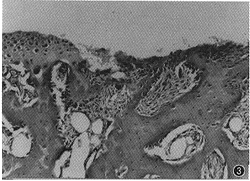

纖維結締組織其它輔助檢查:

FFA檢查可清楚顯示其虹膜血循環情況,虹膜表面的新生血管呈不規則線狀或網狀,可以伴有不同程度的螢光素滲漏。比較明顯的虹膜表面的新生血管,裂隙燈檢查就可以發現。